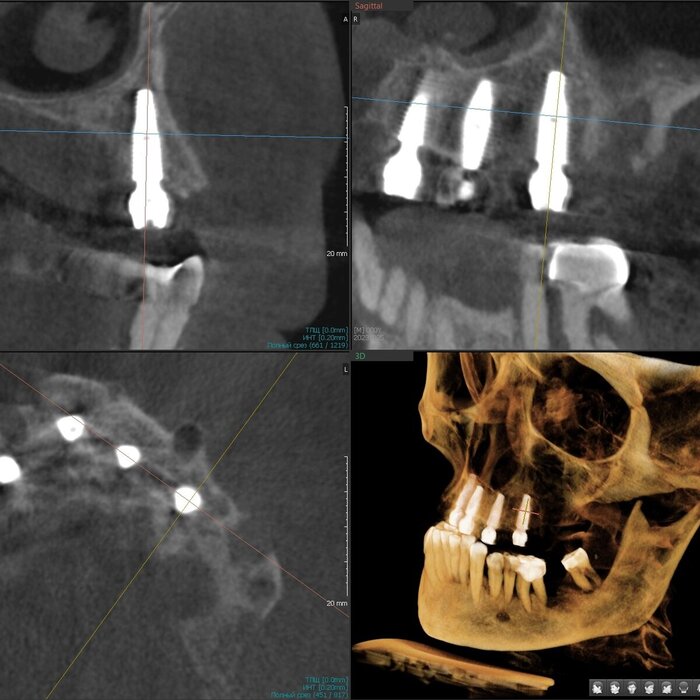

Имплантаты установлены - 5 штук. Были мысли насчёт 6-ти, даже шаблоны сделаны с этим расчётом. Но - обильное кровотечение и малек количество кости не оставили шансов. Мы не рискуем. Делаем на 5-ти, 6-ой имплантат будет установлен позже, через несколько месяцев.

Делаем промежуточное фото. Это нужно, что бы хирург видел, есть ли необходимость имплантаты "докрутить". Да, есть - 2 штуки можно углубить на 2 мм каждый.

Ещё раз контроль - финишный.

Давайте посмотрим на каждый имплантат - на все 5 штук.

1. Область зуба 2.4.

2. Область зуба 2.2

3. Область зуба 1.2

4. Область зуба 1.4

5. Область зуба 1.7

Всё хорошо. Всё отлично. У Егора Романовича настоящий талант, опыт, знания и, к тому же, искренняя любовь к своему делу.